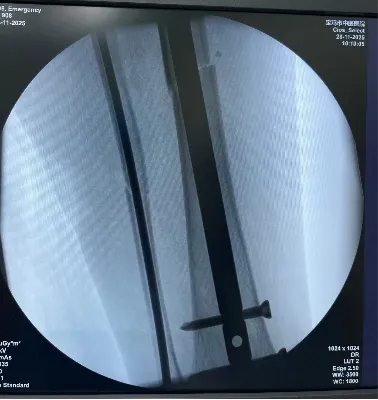

针对患者病情,骨伤中心3病区(环骨盆专科)团队全面评估伤情并制定周密手术方案。手术全程遵循微创理念,实现骨折闭合复位内固定治疗。最大伤口仅为膝关节上方长约3cm,通过数个1cm的小切口完成,手术时间不到1小时,术中出血量不足30毫升,最大限度降低了手术创伤,伤口美容缝合,术后无需拆线,充分体现了精准医疗与微创技术的优势。

该技术相比传统手术方法,具有显著优势:它避免了在骨折处做大切口,仅通过髌骨上方及膝关节、踝关节周围的小切口,在X线精确定位下完成骨折复位和固定,从而最大限度地减少了对周围皮肤和软组织的损伤,降低了术后感染和皮肤坏死的风险,加速患者的康复进程。